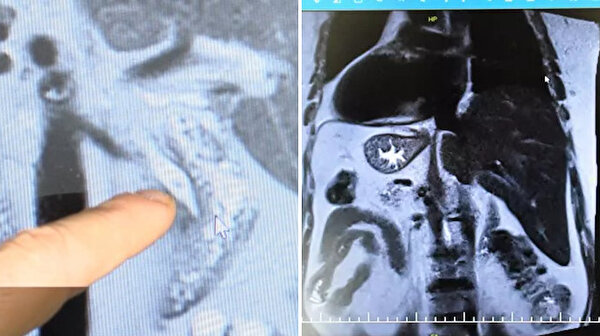

Gaziantep’te mide ağrısı şikâyetiyle hastaneye başvuran 66 yaşındaki Evin Aslan, yapılan tetkikler sonrası hayatının en büyük şaşkınlığını yaşadı. Yıllardır kalbinin sağ tarafta attığını söylediğinde kimseyi inandıramayan Aslan’ın, aslında tüm iç organlarının ters yönde konumlandığı ortaya çıktı.

Uzun süredir mide ağrıları yaşayan ve ardı ardına hastanelere gitmesine rağmen net bir tanı konamayan Aslan, son olarak Gaziantep Şehir Hastanesi’ne başvurdu. Burada yapılan detaylı incelemelerde Aslan’ın kalbinin sağda, midesinin ve dalağının yine sağ tarafta; karaciğer ve safra kesesinin ise solda olduğu tespit edildi.

“Hasta karın ağrısı şikâyetiyle geldi. MR görüntülemede tüm organların tam tersi şekilde yerleştiğini gördük. Aynı zamanda safra kanalında taş vardı ve tekrarlayan pankreatit atakları geçiriyordu. RCP işleminde hastayı ters pozisyonda almak zorunda kaldık. Oldukça zorlu bir işlem olmasına rağmen başarılı bir şekilde tamamladık” dedi.